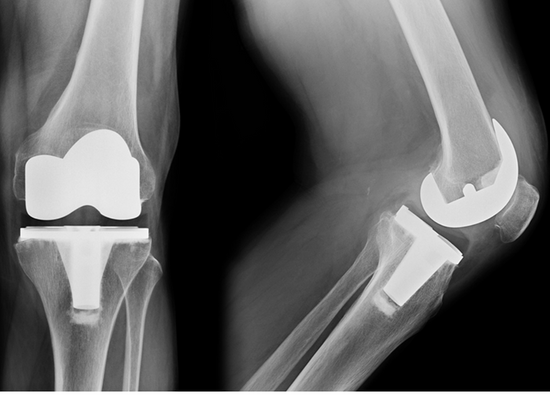

Revision Knee Replacement

Sometimes a knee replacement procedure may fail after some time. It could be due to infection, injury, loosening or instability. You may have a failed knee replacement if:

This condition can only be corrected by a Revision Knee Replacement surgery. This procedure is done to replace the failed implant with a new prosthesis.